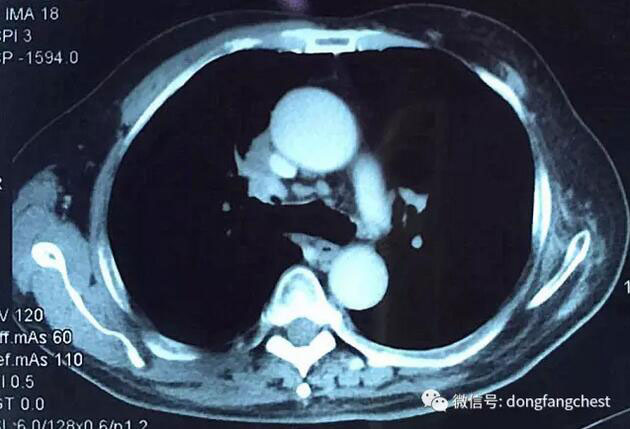

化疗后,李老体内的肿瘤体积明显缩小,随后于2月22日进入总院心胸外科进行手术治疗。手术由总院胸外科朱胜主任、王鸿副主任、高涛涛医生共同完成。术中发现肿瘤侵犯右肺动脉干、上腔静脉部分血管壁。术中,经上腔静脉远端、右心房插管转流,阻断受肿瘤侵犯部位腔静脉后予以部分血管壁切除,然后取心包组织进行上腔静脉修补重建。

手术后胸片肺复张良好,可以自主生活,状态平稳,待明天拆线后,即可出院。